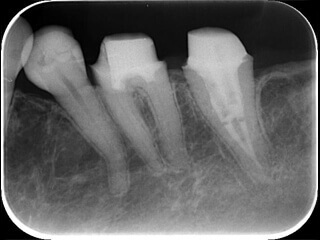

症例4 土台が大きくて治療できないようだ

15

太い金属(白く写っている部分)が入っており、その先の骨が溶けてます。

16

太い金属を安全に外し根の治療を終えました。骨は再生しています。

この治療のリスクと費用

精密根管治療前歯 ¥154,000(税込)

根管治療後に歯ぐきの腫脹や痛みを伴うことがあります。

虫歯の範囲が大きい場合、残りの歯が薄くなり歯が割れてしまう可能性があります。